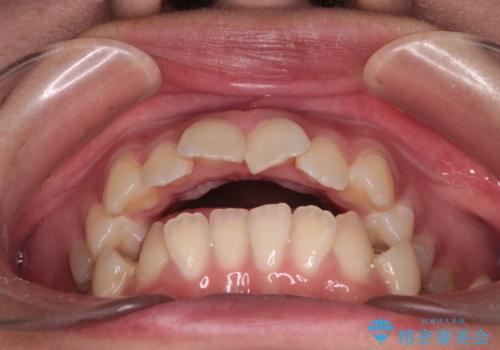

【インビザライン】シザーズバイト、抜歯矯正

- オープンバイトを主訴に来院された患者様です。

抜歯を行うことで、インビザラインを用いて前歯を下げることができ、同時にオープンバイトを改善することができました。